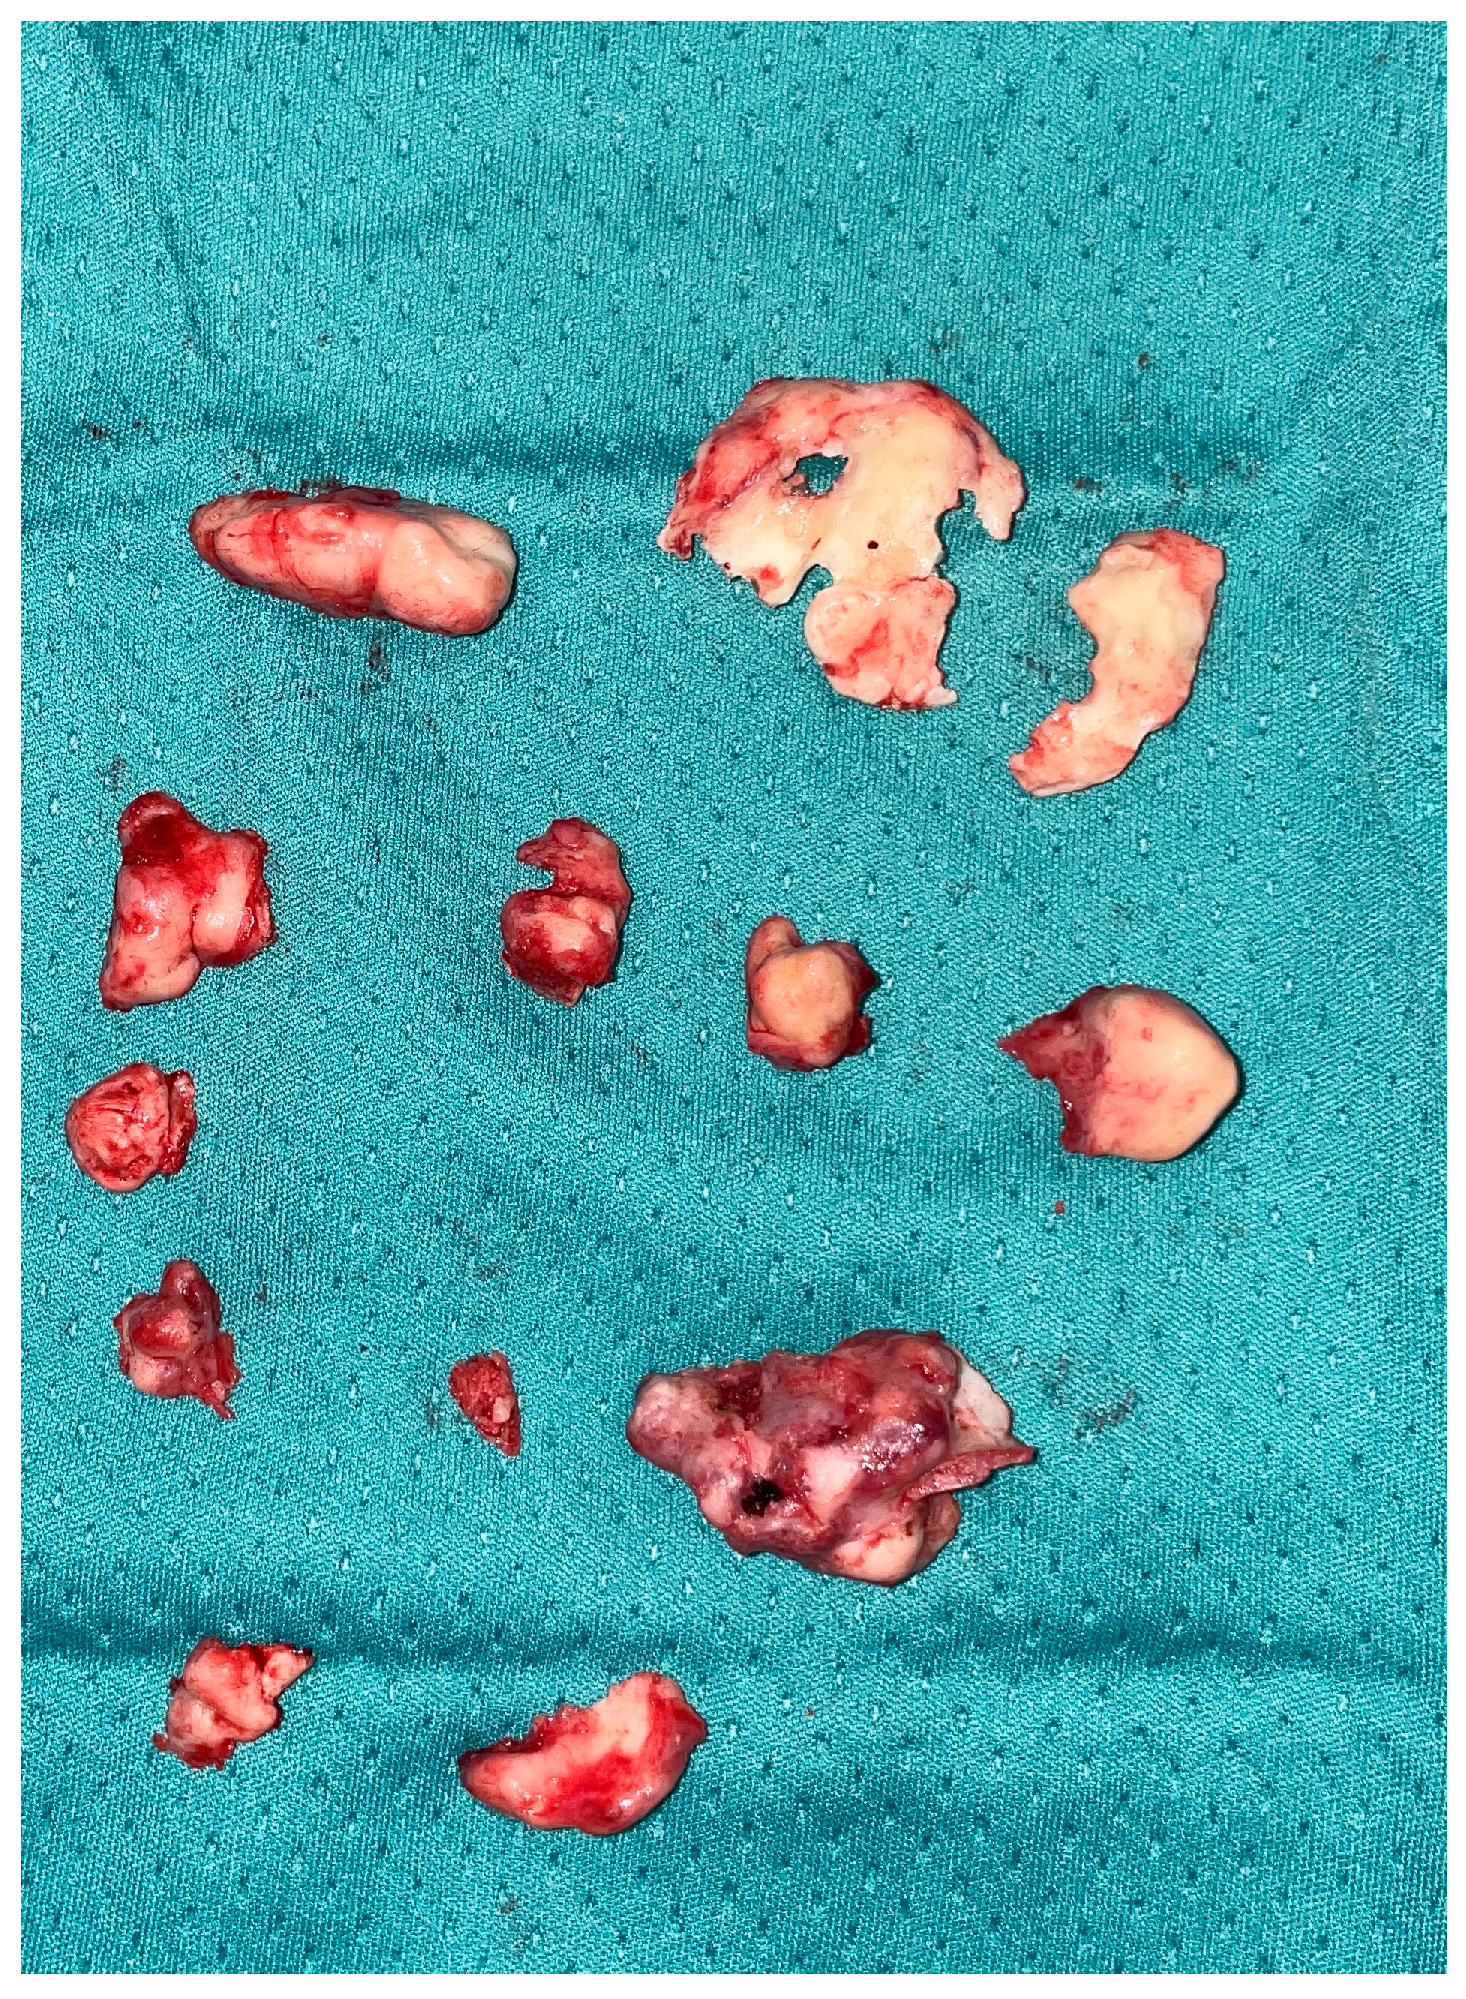

After this first phase of ‘open’ surgery, we moved on to the endoscopic phase by which the nasal cavities were explored bilaterally. On the right, the inferior turbinate appeared with a completely subverted structure invading the entire right nasal fossa; using a drill, the turbinate was detached and sent in its entirety for histological examination (Figure 5).

Figure 5.

Intra-operative samples. All the fragments removed during the surgery are appreciated.